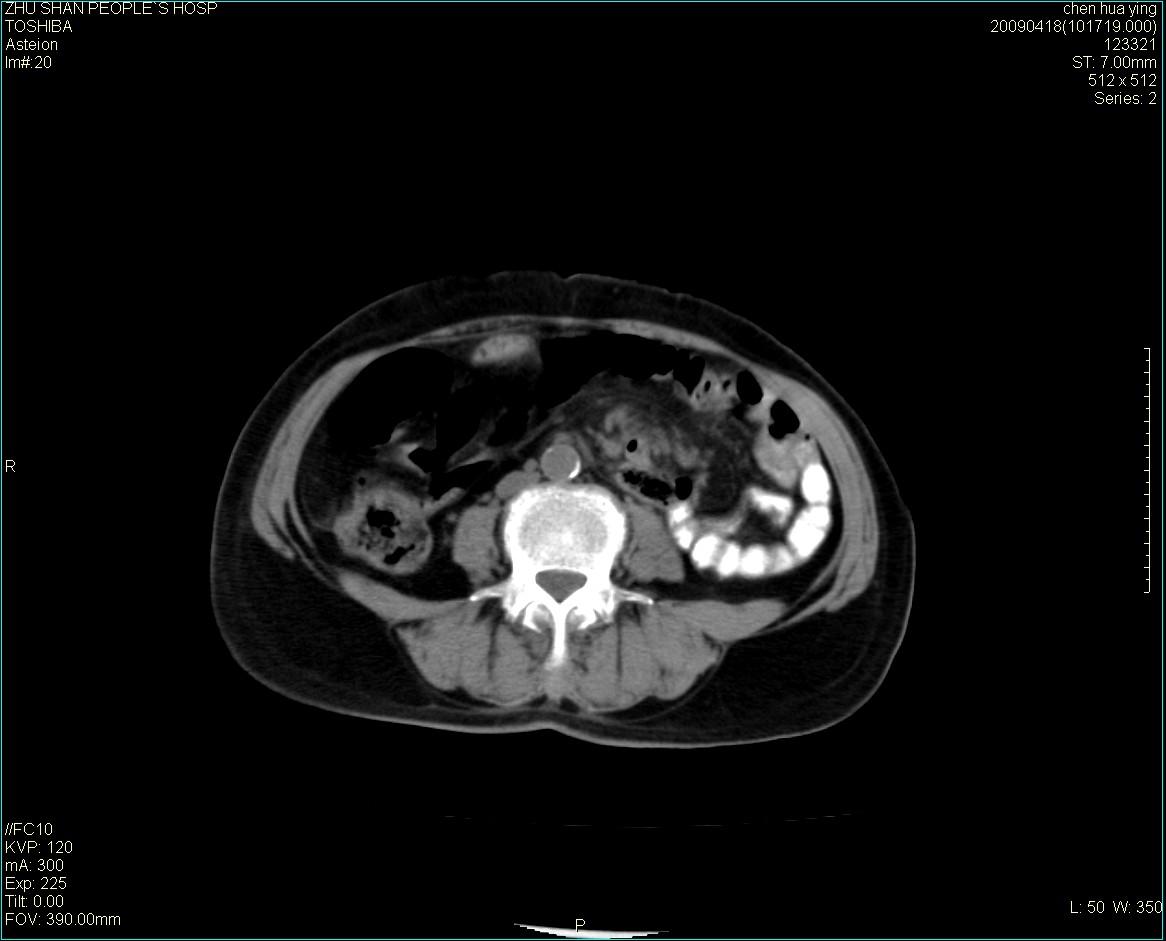

女性病人 65岁 腹部包块半年余结肠造影未见异常.

病灶略呈圆形有分叶状,上部层面呈实性,右侧见圆形低密度区,灶内见团块状钙化,病灶下方与肠管分境不清,考虑间质瘤可能性大,建议肠道准备后增强